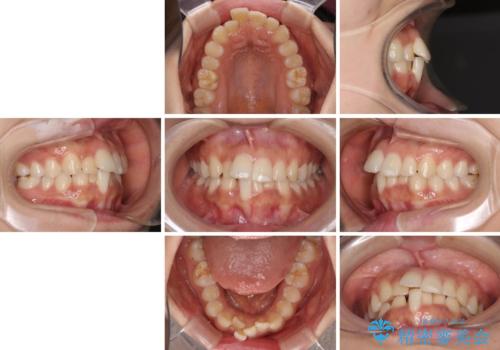

- 患者様

- 20代女性

- 飛び出した前歯と全体的なデコボコを気にして来院された患者様です。

ワイヤーでもマウスピースでも治療可能でしたが、自己管理の重要なマウスピース矯正は自分には向かないとのことで、ワイヤー矯正で治療することとしました。

上下歯列全体を後方に移動させるため、親知らずは全て抜歯することにしました。